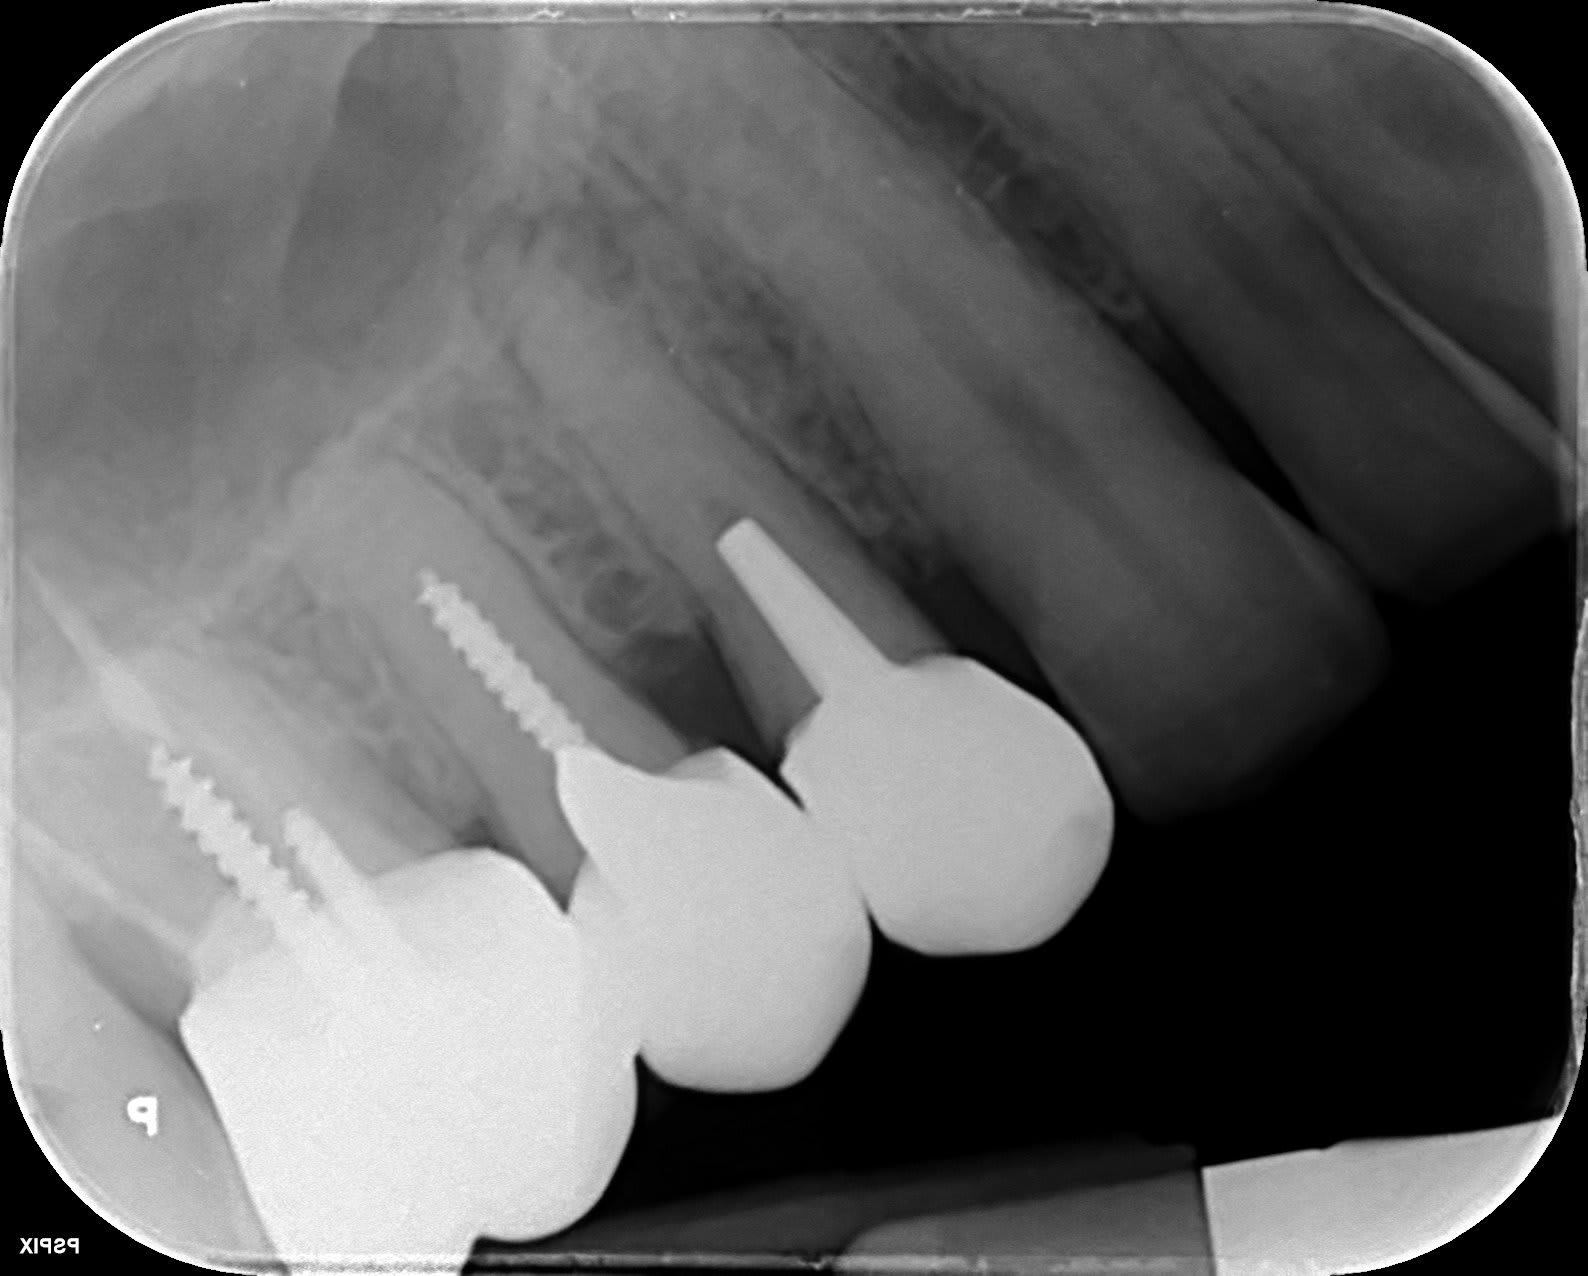

Des fois c'est bizarre. Patient, vient pour douleur molaire sup, irradiante, qui a duré un jour, va mieux.

Ricaud 14 rqxbql - Eugenol

Ricaud17 pvv0vr - Eugenol

Forcément la pêche sur 14 attire l’œil. L'élargissement apex 15 aussi.

Mais si épisode infectieux ça ne dure pas une journée... c'est pas l'origine des douleurs. Il y a des soucis à venir OK:-)

RX secteur 4 et bingo... 47 carie juxta pulpaire pouvant expliquer des douleurs par crises irradiantes.

Voili, voilà...

Ricaud47 c5coje - Eugenol